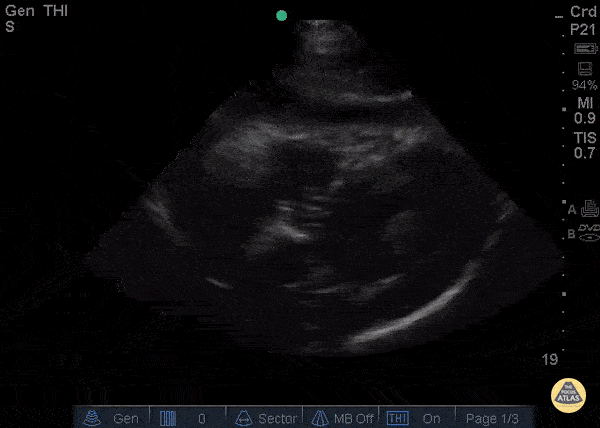

Pericardial Disease - Exudative Effusion

A 67y/o M PMH ESRD presented to the ED with recurrent sharp chest pain, cough, and fever that were reported during routine dialysis. He had been recently hospitalized for chest pain one week prior and diagnosed with pericardial effusion. Upon repeat presentation to the ED, the patient’s vital signs and examination were unremarkable. ECG showed diffuse PR depressions and ST elevations. PoCUS (cardiac subcostal view shown) demonstrated a circumferential, anechoic pericardial fluid collection with septations; there was no evidence of tamponade. The patient was started on indomethacin and colchicine and admitted to the CCU. A few days later, cardiothoracic surgery performed a pericardial window, drained 350 ml of serosanguinous fluid, and lysed multiple adhesions. Biopsied tissue revealed a thickened, inflamed pericardium with abscess and granulation tissue formation. Pericardial fluid testing was negative for bacteria, fungi, acid-fast bacilli, and malignancy. Emergency physicians can detect pericardial effusion with a sensitivity of 96% (95% confidence interval [CI] 90.4% to 98.9%), specificity of 98% (95% CI 95.8% to 99.1%).[i] High risk features that warrant hospital admission include temperature > 38°C, subacute course, large effusion (echo-free space > 20 mm), tamponade, and lack of response to aspirin or non-steroidal anti-inflammatory drug therapy; however, the etiology often remains a mystery. [ii] The presence of a loculated effusion on echocardiography may suggest the eventual need for surgical intervention with pericardiectomy or pericardial window.[iii] Dr. Ian Desouza - Kings County Emergency Medicine [i] Mandavia DP, Hoffner RJ, Mahaney K, Henderson SO. Bedside echocardiography by emergency physicians. Ann Emerg Med 2001;38:377-82. [ii] Imazio M, Cecchi E, Demichelis B, et al. Indicators of poor prognosis of acute pericarditis. Circulation 2007;115:2739-44. [iii] Imazio M, Spodick DH, Brucato A, Trinchero R, Adler Y. Controversial issues in the management of pericardial diseases. Circulation 2010;121:916-28.